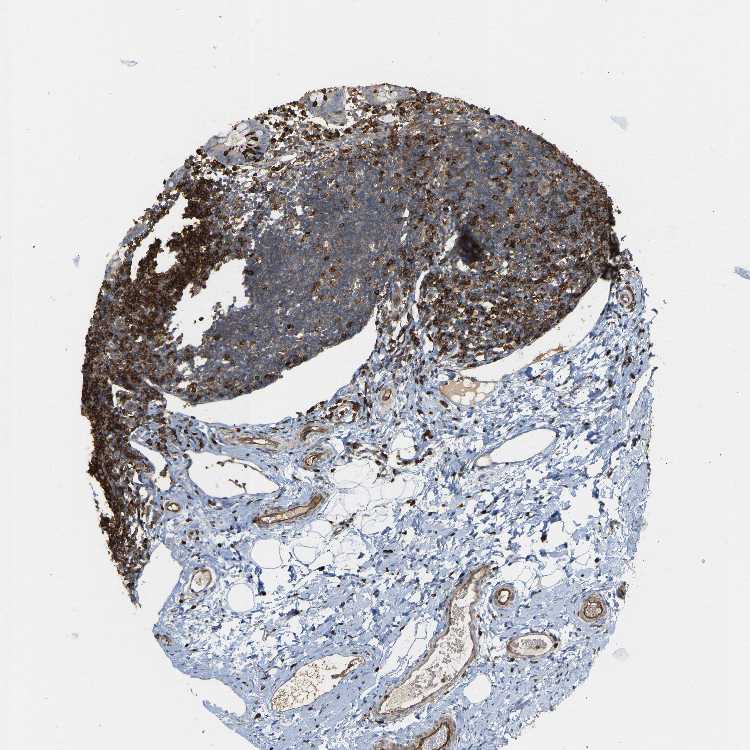

APPENDIX - Expression summary

Protein expression

Appendixi

On the top, protein expression in current human tissue, based on all annotated cell types, is reported with the units not detected (n), low (l), medium (m) and high (h). Underneath, protein expression in each annotated cell type are reported using the same units.

Protein expression data is based on knowledge-based annotation. For genes where more than one antibody has been used, a collective score is set.

APPENDIX - Antibody stainingi

Antibody staining in the annotated cell types in the current human tissue is reported as not detected, low, medium, or high, based on conventional immunohistochemistry profiling in selected tissues. This score is based on the combination of the staining intensity and fraction of stained cells.

Each image is clickable and will lead to virtual microscopy that enables deeper exploration of all samples and also displays staining intensity scores, fraction scores and subcellular localization as well as patient and tissue information for each sample.

Antibody HPA020099Antibody HPA020100Antibody CAB004280

Glandular cells Not detectedNot detectedMedium

Lymphoid tissue HighHighHigh